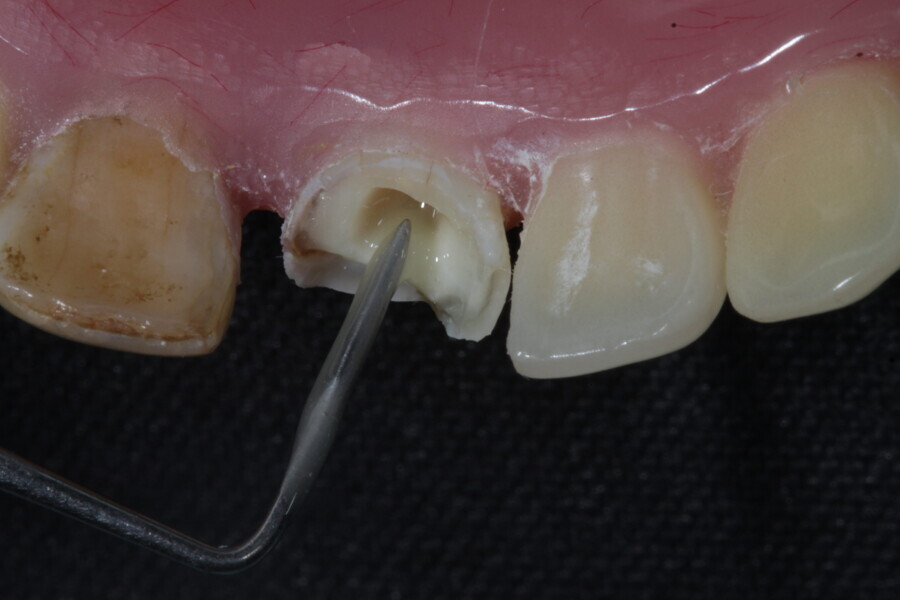

1. functional and aesthetic reconstruction of a maxillary anterior tooth using fibre-reinforced flexible micro-posts after endodontic treatment (Figs. 3–20);

Example 1—showing functional and aesthetic reconstruction of a maxillary anterior tooth using fibre-reinforced flexible micro-posts after endodontic treatment.